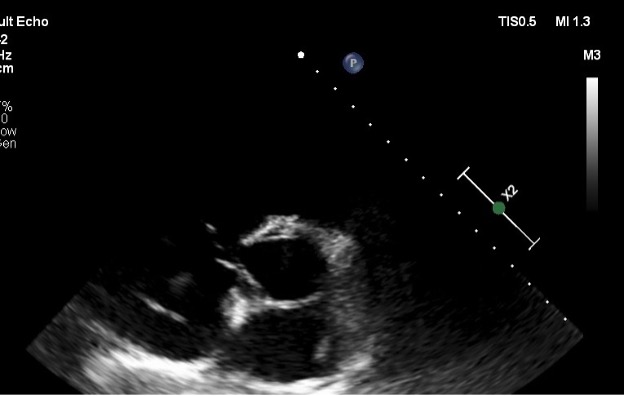

Pulmonar tromboemboliya nəticəsində açıq oval dəliyə pərçimlənmiş tromb kütləsi Dərc edilib: Cild 23, Nömrə 1, 2023 / Nəşr tarixi: 14.10.2023

Şəxanə Ələsgərli, Gulay Məmmədova